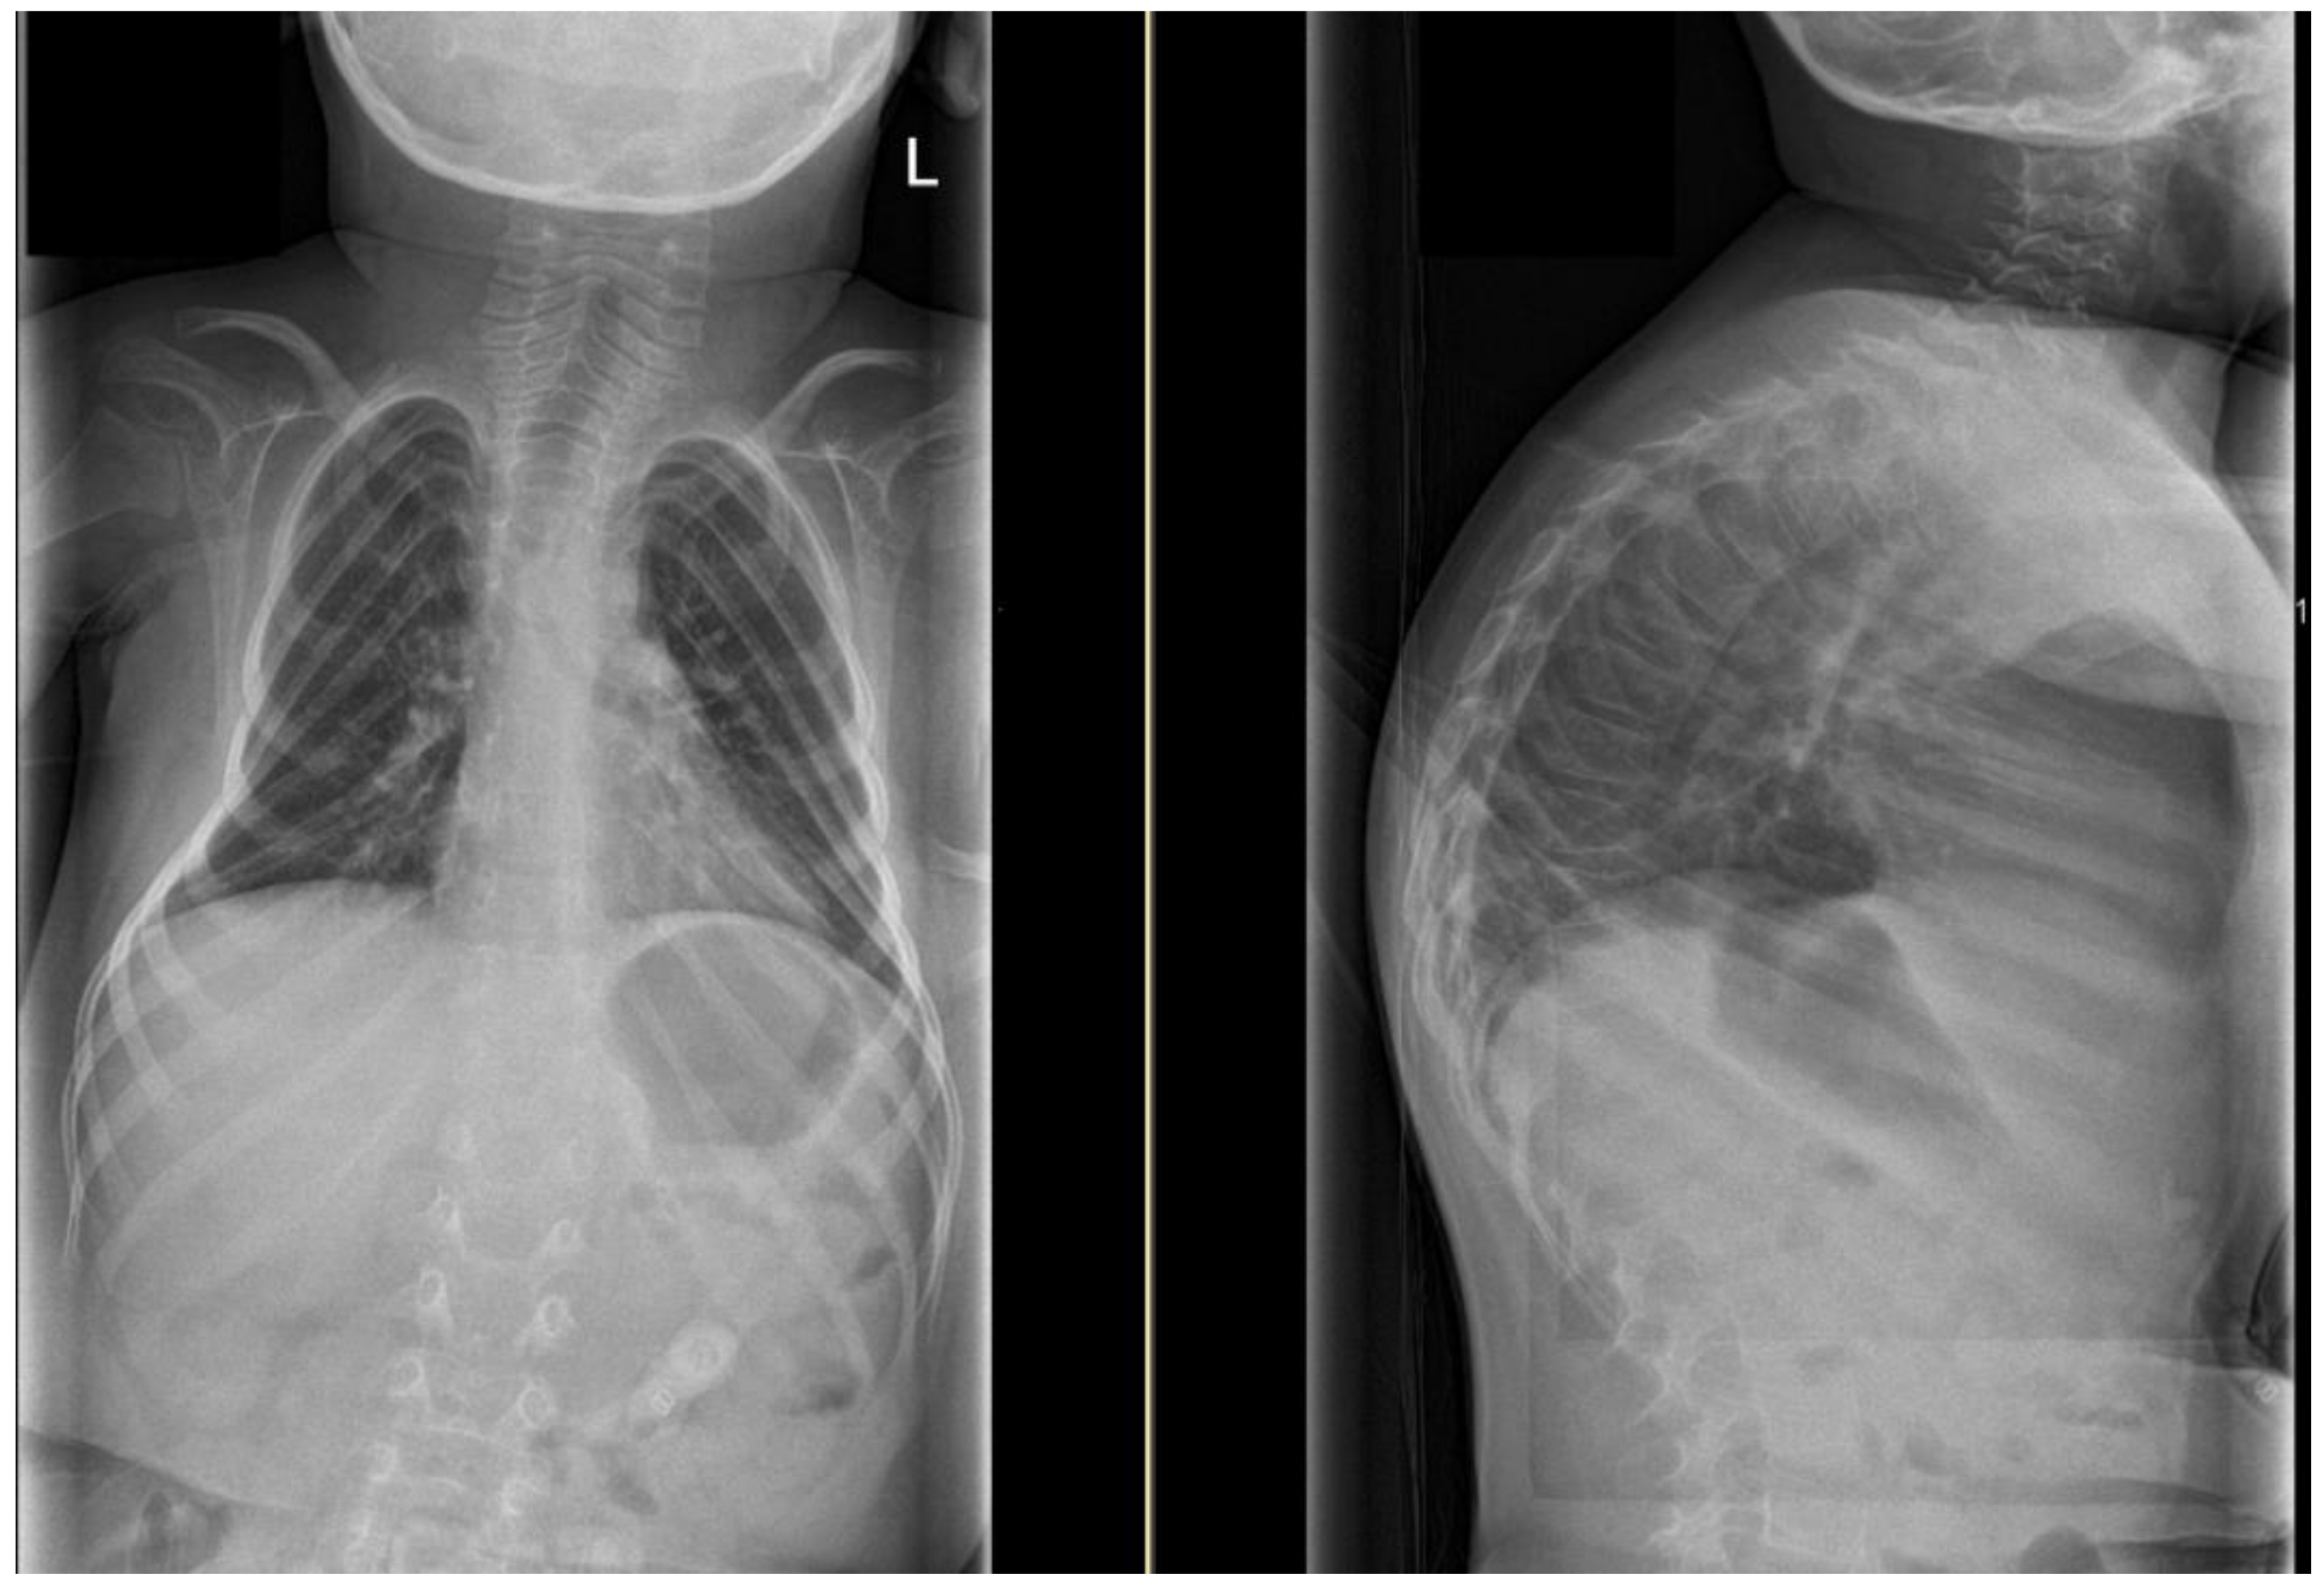

| ID | Scoliosis Type | Scoliosis Curvature Angle (°) | Kyphosis Curvature Angle (°) |

|---|---|---|---|

| 1 | S-type | 29 | |

| 2 | S-type | 43 | 66 |

| 3 | no | 7 | 86 |

| 4 | no | 6 | |

| 5 | no | 0 | 70 |

| 6 | no | 0 | |

| 7 | left convex C-type | 69 | 75 |

| 8 | left convex C-type | 24 | |

| 9 | left convex C-type | 52 | 60 |

| 10 | left convex C-type | 21 | |

| 11 | no | 5 | |

| 12 | no | 7 | 48 |

| 13 | no | 7 | 94 |

| 14 | left convex C-type | 64 | 73 |

| 15 | right convex C-type | 82 | 76 |

| 16 | S-type | 35 | 45 |